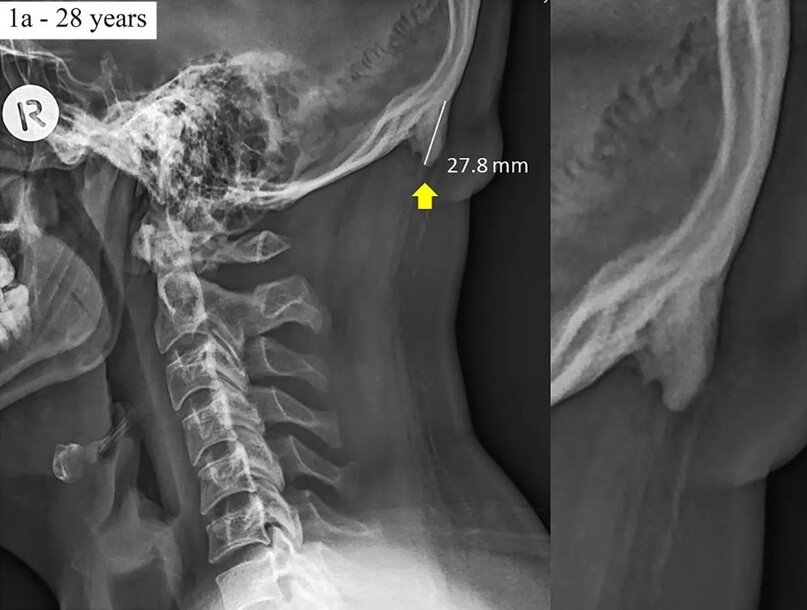

Все началось с того, что 28-летнему мужчине сделали рентген, в результате которого обнаружили у него костный отросток в черепе, почти в три сантиметра длиной.

Это изображение включили в научную работу 2018 года, которую создали два австрийских исследователя. В ней они связали так называемые «костные шпоры» на черепе с тем, что наше поколение проводит большое количество времени, уткнувшись в экраны телефонов. Как утверждают исследователи, нарост на задней части черепа расположен у многих из нас там, где голова встречается с шеей. По их словам, его даже можно почувствовать.